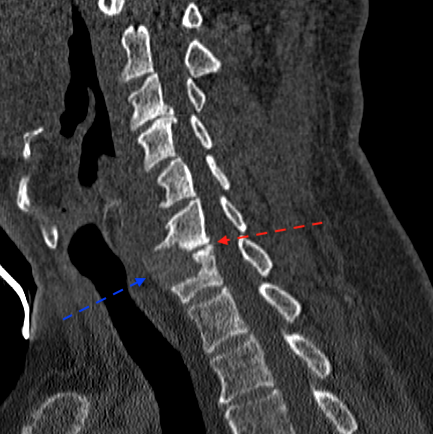

En TC sagital se aprecia ausencia de fusión y ubicación de la caja en mitad anterior (incluso con extensión parcial)

La flecha azul marca el espacio que ocupa la prótesis, la flecha roja la estenosis foraminal